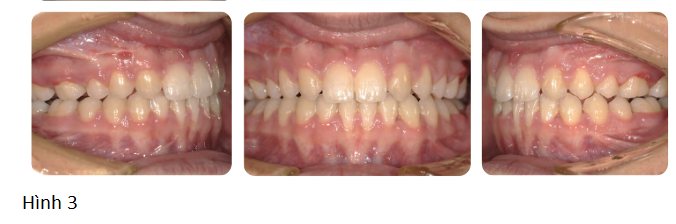

Kết quả cuối cùng được thể hiện ở hình 3.